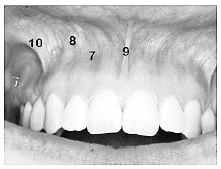

Analise a imagem abaixo.

Podemos afirmar que o número 10 indica o(a):